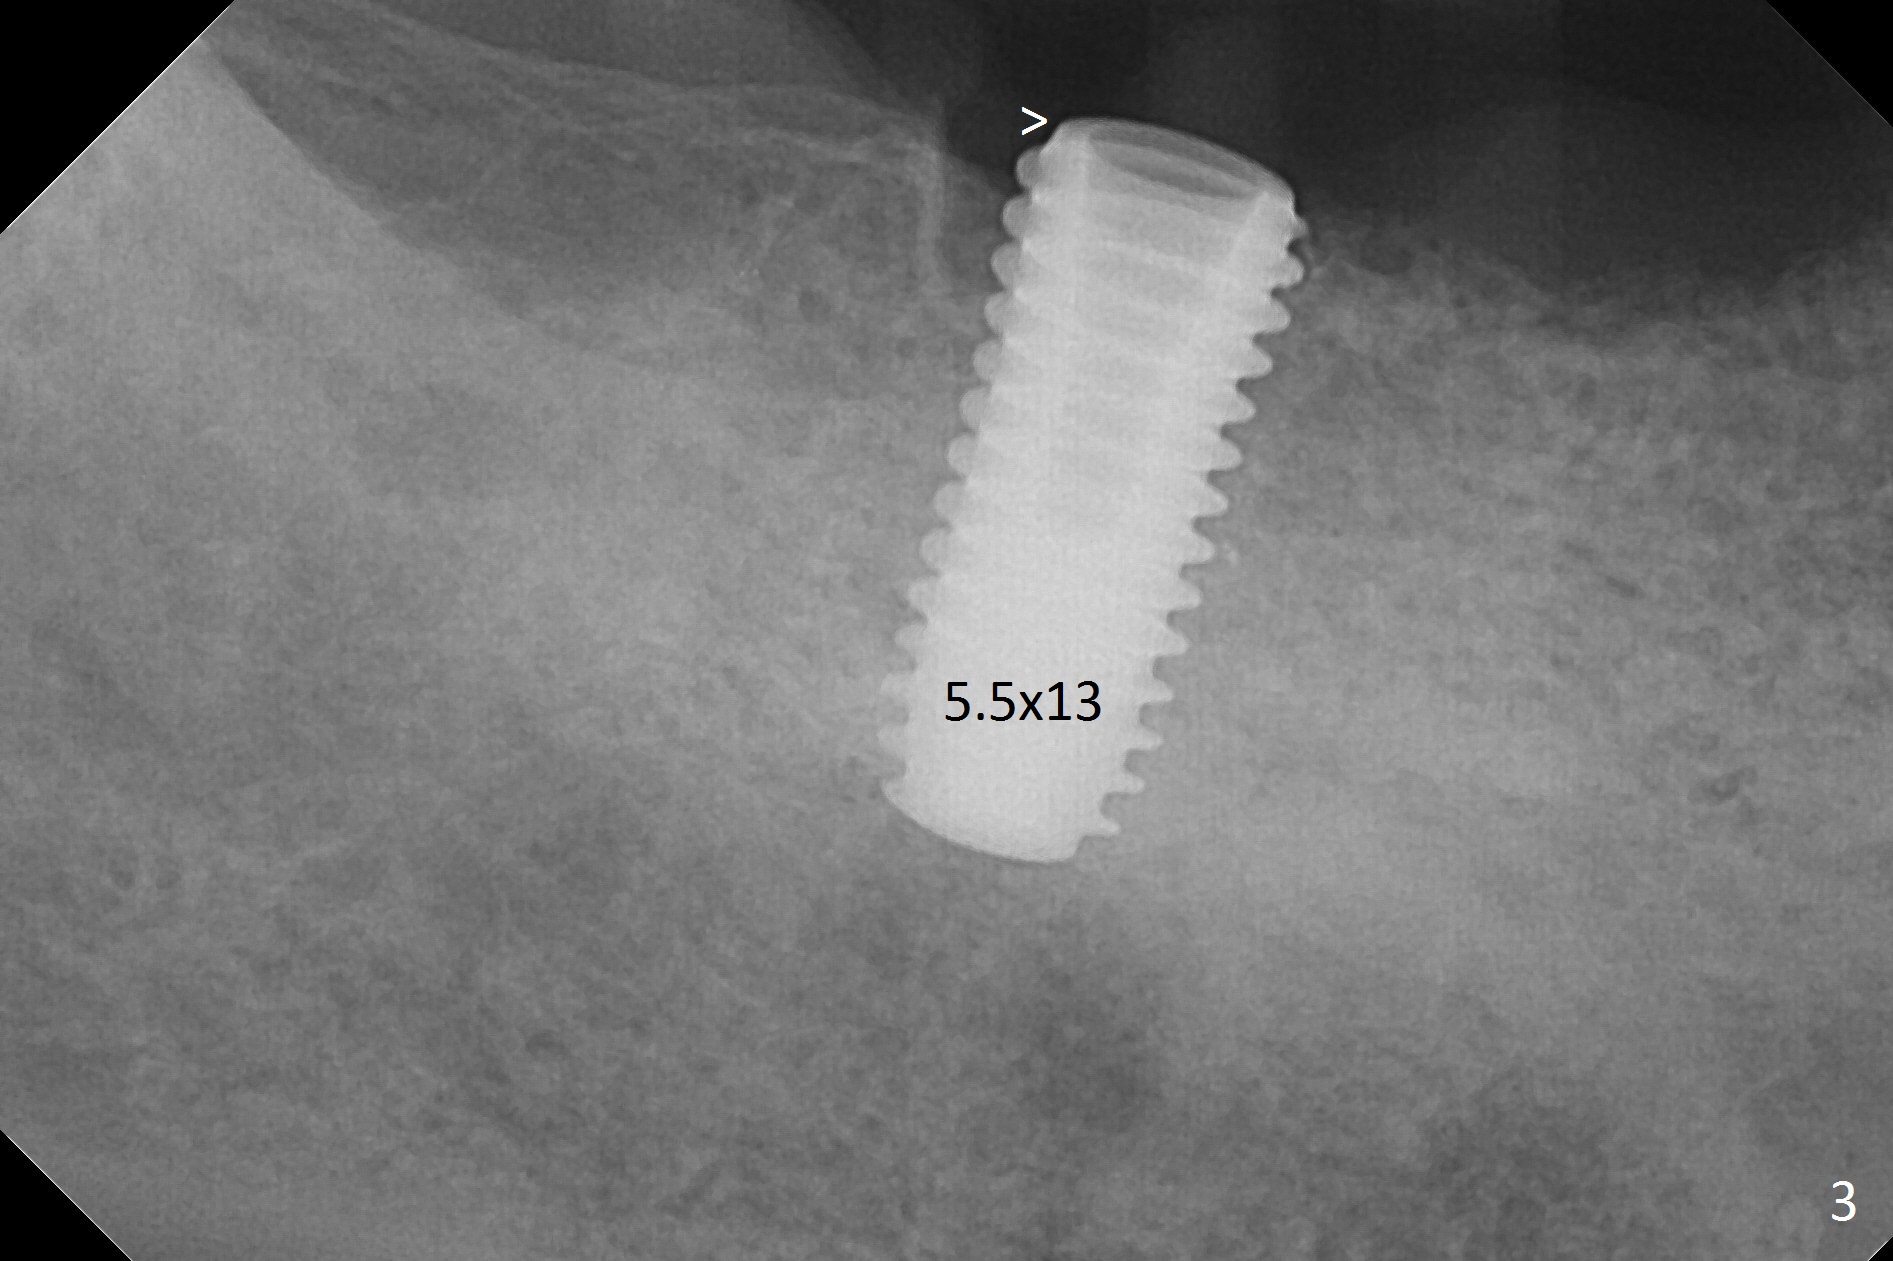

There are 2 challenges associated with #31 implant placement: indistinct Inferior Alveolar Canal (Fig.1-4) and difficulty in fabrication of a provisional (Fig.5). After placing a 5.5x13 mm implant (Fig.3 supracrestal (<)), it is removed for apical resection for ~ 2 mm; when it is reseated, it is subcrestal (Fig.5 <). A simplified temporary provisional (Fig.5 P) is fabricated around a 6.5x4(4) mm abutment (A) without adapting the lower RPD. The patient is advised not to wear the latter. When the socket heals, there will be 2 options: no provisional or a new one. The latter should have good retention to the abutment and no contact with the lower RPD in and out.